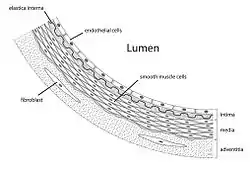

In the context of cardiovascular disease, AGEs can induce crosslinking of collagen, which can cause vascular stiffening and entrapment of low-density lipoprotein particles (LDL) in the artery walls. AGEs can also cause glycation of LDL which can promote its oxidation.[13] Oxidized LDL is one of the major factors in the development of atherosclerosis.[14] Finally, AGEs can bind to RAGE (receptor for advanced glycation end products) and cause oxidative stress as well as activation of inflammatory pathways in vascular endothelial cells.[13][14]

- Increased vascular permeability.

- Increased arterial stiffness

- Inhibition of vascular dilation by interfering with nitric oxide.

- AGEs have specific cellular receptors; the best-characterized are those called RAGE. The activation of cellular RAGE on endothelium, mononuclear phagocytes, and lymphocytes triggers the generation of free radicals and the expression of inflammatory gene mediators.[28] Such increases in oxidative stress lead to the activation of the transcription factor NF-κB and promote the expression of NF-κB regulated genes that have been associated with atherosclerosis.[26]

A receptor nicknamed RAGE, from receptor for advanced glycation end products, is found on many cells, including endothelial cells, smooth muscle, cells of the immune system from tissue such as lung, liver, and kidney. This receptor, when binding AGEs, contributes to age- and diabetes-related chronic inflammatory diseases such as atherosclerosis, asthma, arthritis, myocardial infarction, nephropathy, retinopathy, periodontitis and neuropathy.[30] The pathogenesis of this process hypothesized to activation of the nuclear factor kappa B (NF-κB) following AGE binding.[31] NF-κB controls several genes which are involved in inflammation.[32] AGEs can be detected and quantified using bioanalytical and immunological methods.[33]